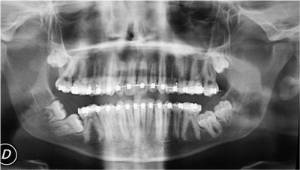

- Tratamientos de las inclusiones dentarias (extracción de cordales o muelas del juicio, extracción de caninos incluidos, extracción de dientes supernumerarios, etc.).

- Cirugía implantológica (colocación de implantes en los maxilares).

- Cirugía sinusal (elevación del seno maxilar, etc.).